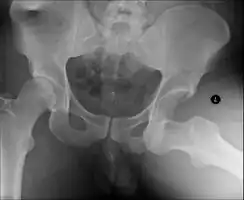

Congenital hip dislocation

Anterior-posterior (AP) X-rays of the pelvis, AP and lateral views of the femur (knee included) are ordered for diagnosis.[13] The size of the head of the femur is then compared across both sides of the pelvis. The affected femoral head will appear larger if the dislocation is anterior, and smaller if posterior.[14] A CT scan may also be ordered to clarify the fracture pattern.